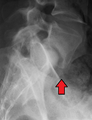

Spondylolisthesis L5/S1. Blue arrow normal pars interarticularis. Red arrow is a break in pars interarticularis